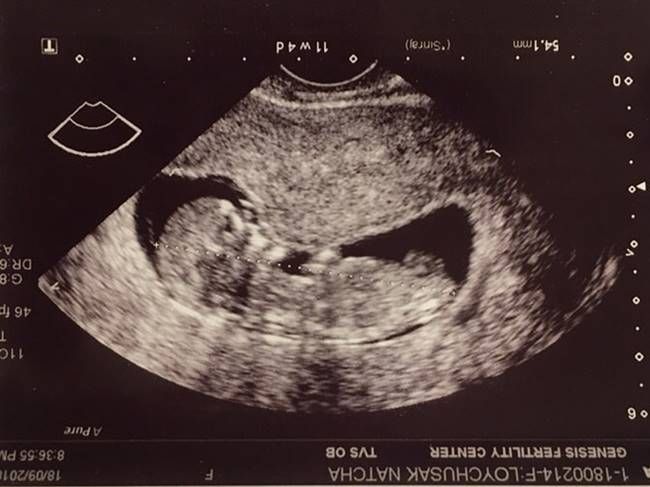

ออกมาประกาศข่าวดีว่าศรีภรรยาคนสวย “ครูก้อย นัชชา” ตั้งท้องสมใจ คุณสามีอย่างนักร้องนักแสดง “เจมส์ เรืองศักดิ์” ก็ออกอาการเห่อหนักมาก คอยดูแลเอาใจศรีภรรยาไม่ห่าง ซึ่งตอนนี้ลูกน้อยในครรภ์ก็มีอายุ 16 สัปดาห์แล้ว

โดยล่าสุดครูก้อย ได้เผยภาพขณะแอทมิดผ่าตัดที่โรงพยาบาล เพื่อเย็บปากมดลูกป้องกันการคลอดก่อนกำหนด พร้อมแบ่งปันประสบการณ์ครั้งนี้ ผ่านอินสตาแกรมอีกด้วย“ฟื้นแล้วค่า 2 ชม. เต็มที่อยู่ในห้องผ่าตัด หมอให้ยาคลายกังวล และยานอนหลับ ก่อนฉีดบล็อคหลัง เลยไม่รู้สึกตัวตอนเย็บเลยค่ะ แต่ตอนนี้ท่อนล่างยังชา ยังขยับไม่ได้เลย อึดอัดมาก ต้องนอนรอสังเกตการณ์ที่ห้องคลอดทั้งคืนค่ะ เพื่อดูการเกร็งตัวของมดลูก ก่อนจะย้ายไปพักที่ห้องส่วนตัวได้ในวันพรุ่งนี้ คุณหมอยังไม่ให้ทานอาหารค่ะ เพราะลำไส้ยังทำงานไม่เต็มที่ เนื่องจากยาบล็อคหลัง หิวมากค่ะ เพราะงดน้ำงดอาหารมาตั้งแต่ บ่ายโมง ขอบคุณสามีที่อยู่เคียงข้างตลอด ไม่เคยโดดเดี่ยวเลย ไม่เคยกลัวเลย ขอบคุณที่สู้ไปด้วยกัน ขอบคุณที่รักก้อยและลูก”